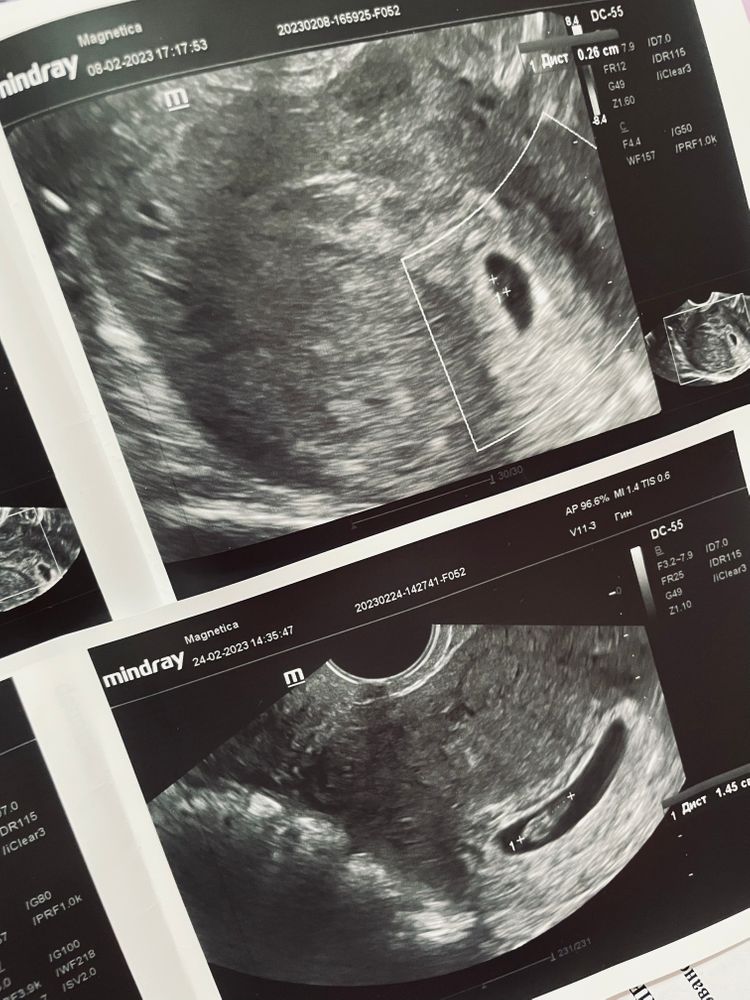

Саша в Зачатие 3 года Второе узи🦐 8ак.недель🤰 Беременность- 1 триместр ( только до 10 недель) Вот и прошли две недели😄 Малыш подрос🦐❤️ Теперь срок 8недель✨ Сердечко нашли😁 и рост 1,45см🥰 Теперь жду узи повторное перед постановкой на учёт, а это уже 3марта! Если не перенесут из-за больничного🤷♀️ Я всё такая же ленивая и хочу постоянно еды🧟♀️😄 Посмотрите еще 20 записей на эту тему Лучший ответ Елена Игоревна Я тебя поздравляю) 24.02.2023 Ответить Отменить Ответить ЮляП Супер,поздравляю) 💕 24.02.2023 Ответить Marta Здрастуйте. Ето у вас акушерская неделя беремености? Или от зачатия? 25.02.2023 Ответить Саша Анастасія , акушерские 26.02.2023 Ответить Мария Как здоровооо 😁 🥳 значит в 8 недель от месячных уже можно рассчитывать на полную картину 💖 эх, время тянется кажется 24.02.2023 Ответить Саша Мария, у меня две недели пролетели😄 я уже потом особо и не ждала😁 24.02.2023 Ответить Беременность 6+6 недель 32 день цикла. Тест + Чаты Беременных Выберите чат: Январята-2026 Февралята-2026 Мартята-2026 Апрелята-2026 Майчата-2026 Июнята-2026 Июлята-2026 Августята-2026